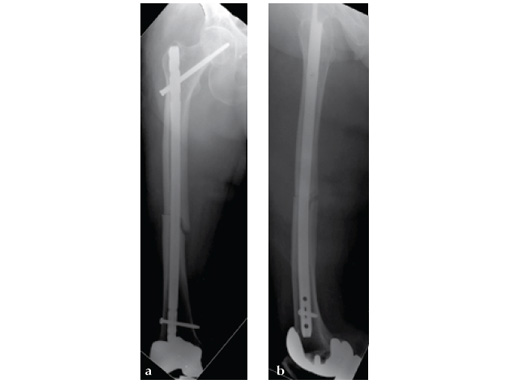

Insertion of A2FN as patient may be suffering from a stress fracture related to long term (2.5 years) bisphosphonate use. My rationale against a plate is because bisphosphonate related fractures will heal extremely slowly. In our experience even despite bone grafting union may need up to 2 years. In that time, a plate will fail in less than a year even if the patient is only allowed very minimal weight bearing.

Note despite the increased in curvature compared to other nails in the market, there is still noticeable malreduction at the fracture site (see Fig 6a-b).

Patient was allowed and achieved immediate weight bearing and in 6 weeks callus is seen at the fracture site (see Fig 7a-b).